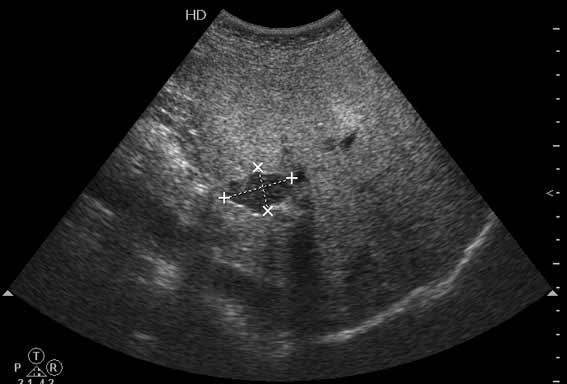

В печени выявлен гипоэхогенный очаг неокруглой формы, аваскулярный при цветовой доплерографии.

Сонограммы, КТ- артериальная, портальная и отсроченная паренхиматозная фазы

Простая и одновременно "сложная" задачка. По УЗИ; явный стеатоз печёночной паренхимы (теперь ключевые слова); на ФОНЕ СТЕАТОЗА определяется гипоэхогенное образование. Варианты? Очаговое образование; и менее вероятно участок гипостеатоза (но не похоже, есть чёткие границе, + не та локализация).

Вывод: надо иметь ввиду, что эхогенность это относительное понятие, эхогенность гемангиомы может изменятся при изменении положения обследуемого пациента (см. прикреплённую статью); не надо забывать что эхогенность образование это понятие относительное, т.е. относительно окружающей паренхимы печени! При стеатозе, гемангиома может выглядеть гипоэхогенно по отношению к гиперэхогенной паренхиме окружающей печени. И главное, есть сомнение-заказываем таргетное мультифазовое КТ.